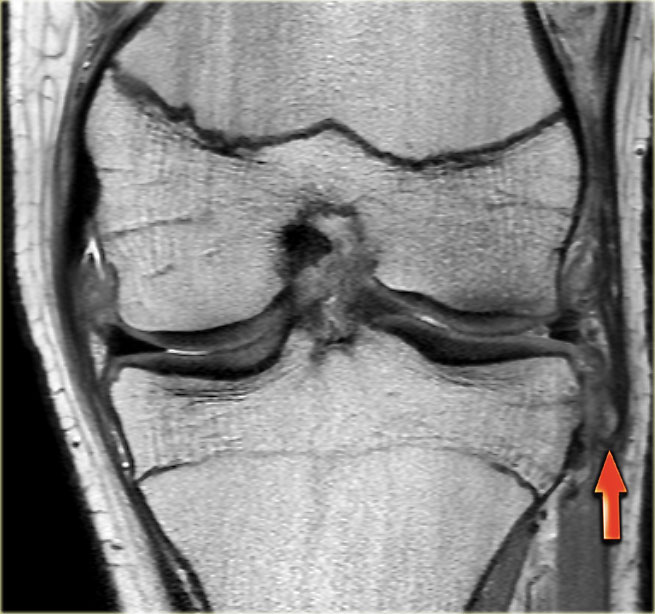

Bên trái là ba lát cắt coronal PD liên tiếp:

-

Rách bó dây chằng bên trong sâu (mũi tên vàng).

Bong mảnh xương ở mặt ngoài đầu gần xương chày, tức là gãy xương Segond (mũi tên đỏ). -

Lưu ý mảnh sụn chêm phía trong bị di lệch.

Điều này cho thấy còn có thêm rách dạng quai xô (bucket handle tear). -

Ngoài rách dạng quai xô (mũi tên xanh phía trong), còn có một đường rách ngang khó nhận thấy ở phần ngoại vi của sụn chêm (mũi tên xanh phía ngoài).

Đường rách ngang này được thể hiện rõ hơn trên các hình ảnh khác (không trình bày ở đây).

Gãy xương Segond gần như là dấu hiệu đặc trưng (pathognomonic) của rách dây chằng chéo trước, điều này cũng được ghi nhận ở bệnh nhân này.